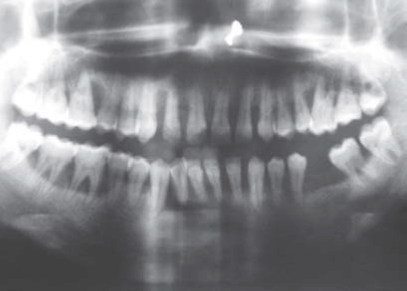

Las radiografías juegan un papel importante en el diagnóstico de la enfermedad periodontal, sin embargo, estas pueden tener limitaciones como en el caso de una la periodontal severa donde no se llegan a observar signos radiográficos de esta. Las proyecciones radiográficas útiles para el diagnóstico en periodoncia incluyen la radiografía periapical, la radiografía de aleta de mordida y la radiografía panorámica; siendo la radiografía periapical con técnica paralela la de principal elección para la evaluación de enfermedad periodontal, ya que la técnica de la bisectriz puede mostrar mayor o menor reabsorción ósea de la cual realmente presenta el paciente. Las radiografías de aleta de mordida tomadas verticalmente pueden utilizarse para evaluar la altura de la cresta ósea, cuando la perdida de esta ha sido considerable, siendo de mayor utilidad para la evaluación postratamiento o como una radiografía de seguimiento. Las radiografías de aleta de mordida tomadas horizontalmente no son útiles para evaluar la reabsorción óseas severas, pero son útiles para la evaluación de caries interproximal o recidivante. Entre las radiografías útiles para la evaluación periodontal, la radiografía panorámica es la de menor precisión ya que solo es útil para una evaluación general del soporte óseo alveolar. No obstante, esta radiografía tiene un campo amplio de evaluación para poder evaluar casos como terceros molares impactados bilaterales comprometiendo el hueso alveolar de una segunda molar o múltiples coronas protésicas desadaptadas y sobreobturaciones que condicionen la pérdida ósea alveolar, aunque en la mayoría de estos casos siempre será necesaria la ampliación del estudio con radiografías periapicales para una mejor evaluación de la zona.